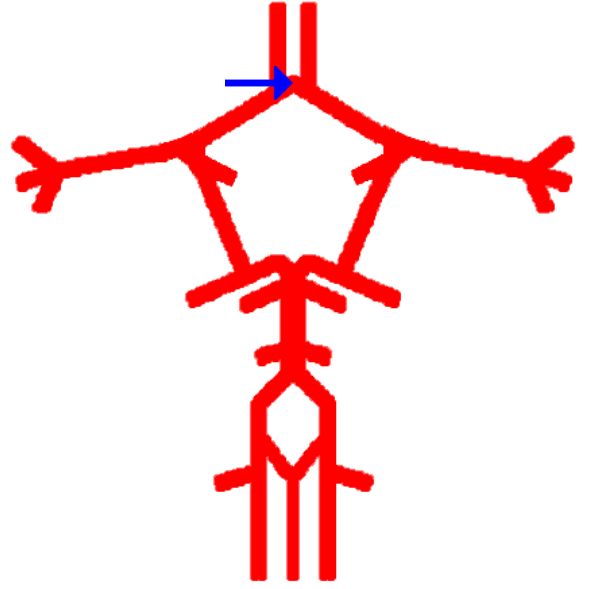

What is this?

Anterior cerebral artery

Anterior communicating artery

Label this cerebral artery